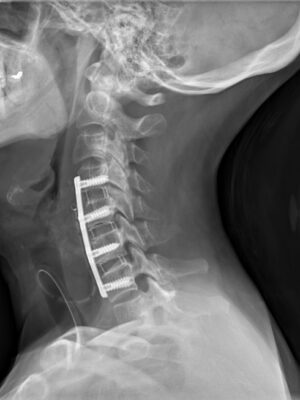

Krční páteř

Krční páteř operujeme nejčastěji z předního přístupu. Příčným řezem v tzv čárách štěpitelnosti kůže (vráskách) se dostaneme k postiženému segmentu páteře. Po odstranění meziobratlové ploténky a osteofytů, které utlačovaly nervové struktury nahradíme vyplníme meziobratlový prostor implantátem vyplněným kostním štěpem odebraným z lopaty kosti kyčelní a obratlová těla fixujeme speciální krční dlahou.

V případech víceetážového postižení krční páteře volíme operační přístup zadní.